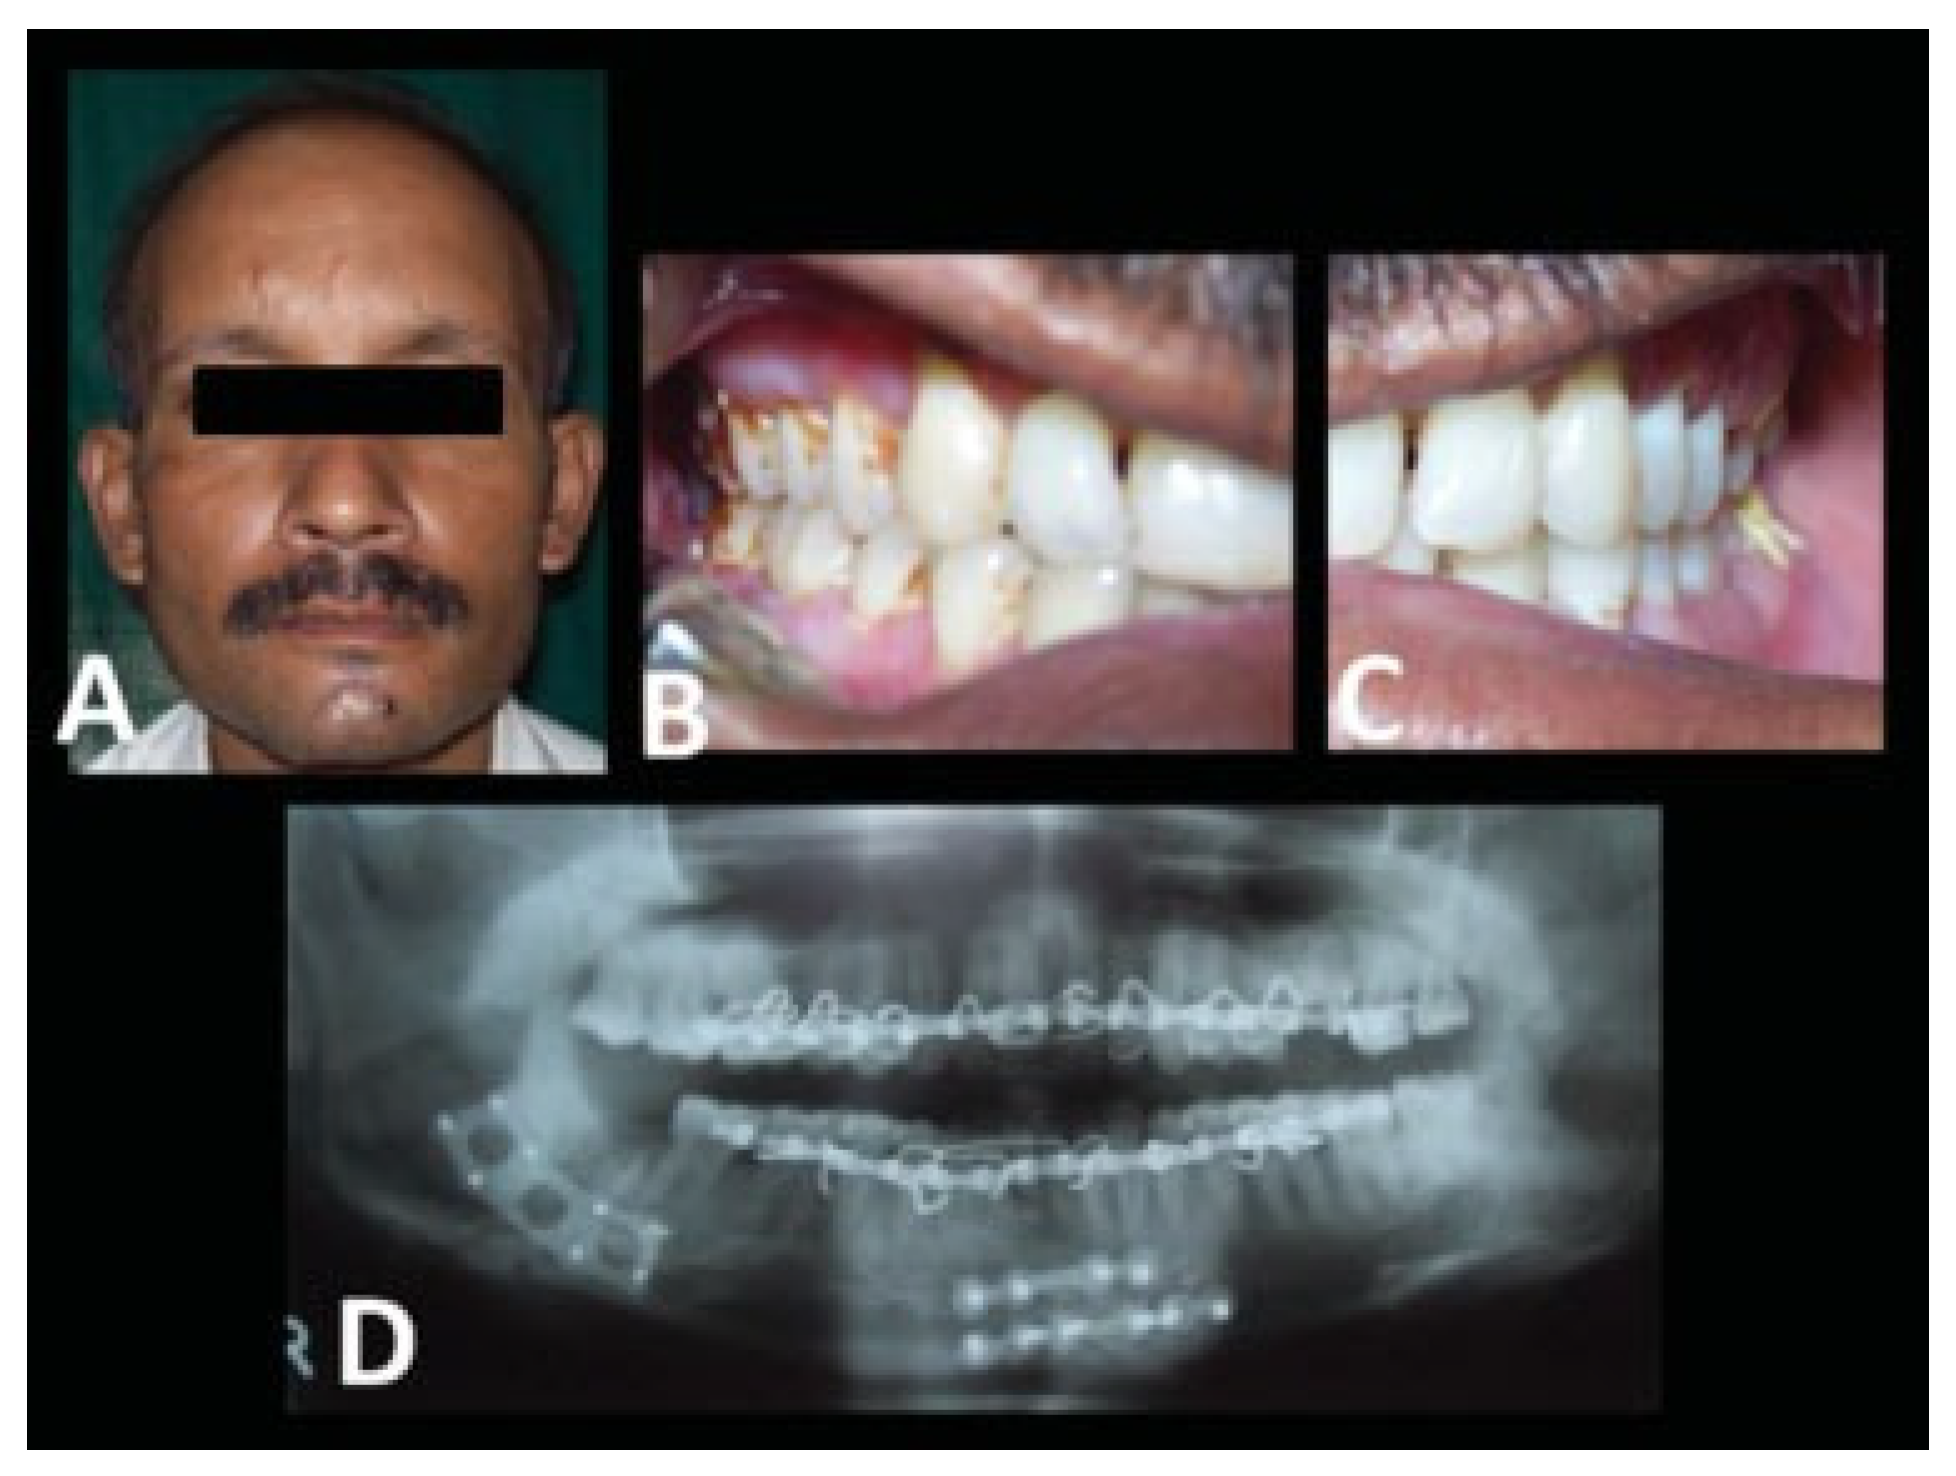

| Case no. | Fractured sites | Displacement | Edema | Paraesthesia/anesthesia | Occlusion status |

| 1 | Rt. parasymphysis and Lt. angle | Displaced | +ve | —ve | Deranged |

| 2 | Lt. angle | Displaced | +ve | —ve | Deranged |

| 3 | Rt. parasymphysis and Lt. angle | Displaced | +ve | —ve | Deranged |

| 4 | Lt. angle | Minimally displaced | +ve | —ve | Deranged |

| 5 | Lt. angle | Minimally displaced | +ve | —ve | Deranged |

| 6 | Lt. body and Rt. angle | Displaced | +ve | +ve | Deranged |

| 7 | Lt. angle | Displaced | +ve | —ve | Deranged |

| 8 | Lt. parasymphysis and Rt. angle | Displaced | +ve | +ve | Deranged |

| 9 | Lt. parasymphysis and Rt. angle | Displaced | +ve | —ve | Deranged |

| 10 | Rt. angle | Minimally displaced | +ve | —ve | Deranged |

| 11 | Rt. angle | Displaced | +ve | —ve | Deranged |

| 12 | Lt. angle | Displaced | +ve | —ve | Deranged |

| 13 | Rt. parasymphysis and Lt. angle | Displaced | +ve | —ve | Deranged |

| 14 | B/l angle | Displaced | +ve | +ve | Deranged |

| 15 | Lt. parasymphysis and Rt. angle | Minimally displaced | +ve | —ve | Deranged |

| 16 | Rt. parasymphysis and Lt. angle | Displaced | +ve | —ve | Deranged |

| 17 | Lt. angle | Displaced | +ve | —ve | Deranged |

| 18 | Lt. angle | Displaced | +ve | —ve | Deranged |

| 19 | Rt. angle | Displaced | +ve | —ve | Deranged |

| 20 | Lt. parasymphysis and Rt. angle | Minimally displaced | +ve | —ve | Deranged |